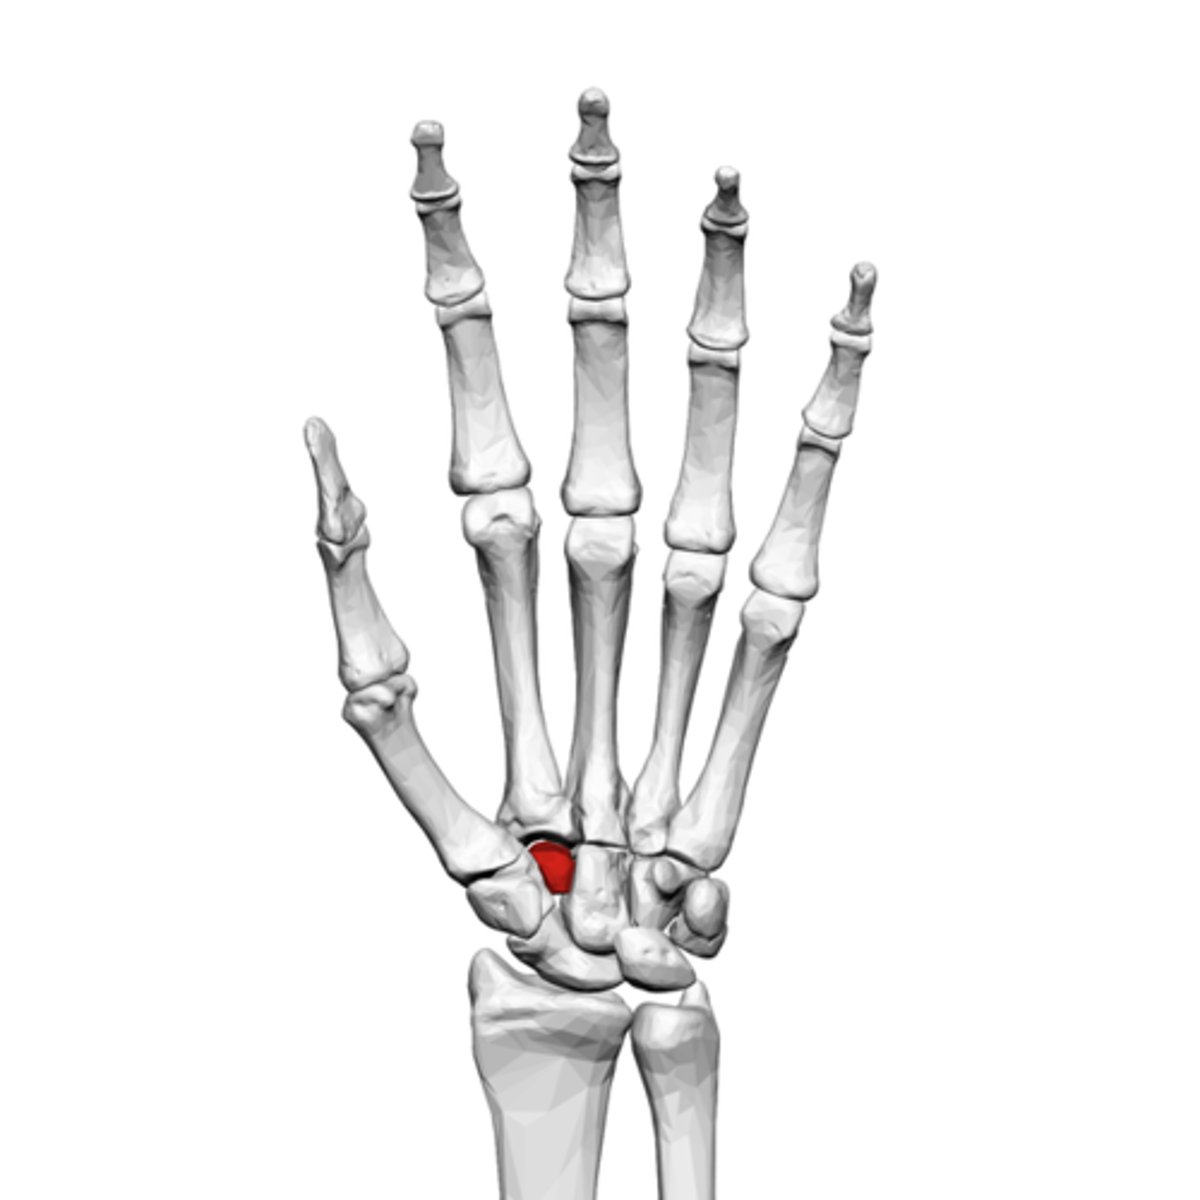

What is the term of the bones highlighted in red?

Lunate

Triquetrum

Pisiform